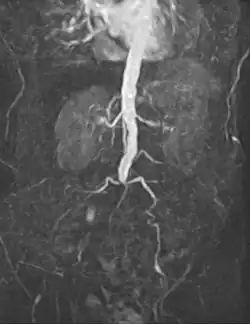

An abdominal aortic aneurysm (AAA) refers to aneurysmal dilation of the aorta confined to the abdominal cavity. Most commonly, aneurysms are asymptomatic and located in the infrarenal position. Often, they are discovered incidentally or on screening exams in patients with risk factors such as a history of smoking. Patients with aneurysms which have a diameter less than 5 cm are at <1% rupture risk per year. When the aneurysm meets size criteria it can be treated with aortic replacement or EVAR.

Abdominal aortic aneurysms can be classified as infrarenal, juxtarenal, pararenal or suprarenal as depicted in the illustration. Abdominal aortic aneurysms can be classified as infrarenal, juxtarenal, pararenal or suprarenal as depicted in the illustration.